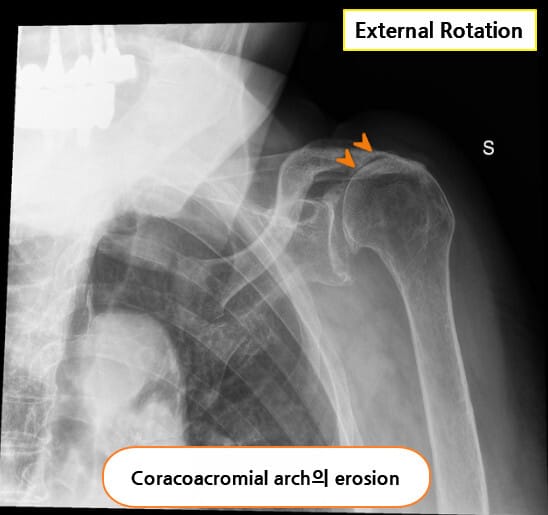

X-ray

회전근개 자체는 관찰되지 않지만, 상완골의 상방 전위(superior migration of humeral head), 견봉하 공간 협소(subacromial space narrowing), 석회화(calcium deposit) 등이 간접적으로 파열을 시사할 수 있습니다.